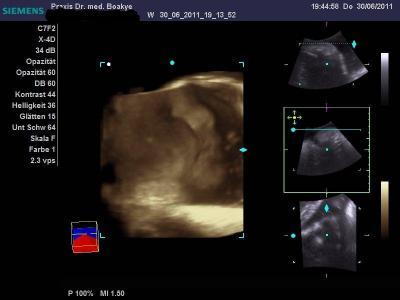

3 D Bild

leider nicht wirklich scharf bzw. man kann es nur schlecht sehen

Und hier nochmal das von vor 2 Wochen aus dem Kh der Schnappschuß